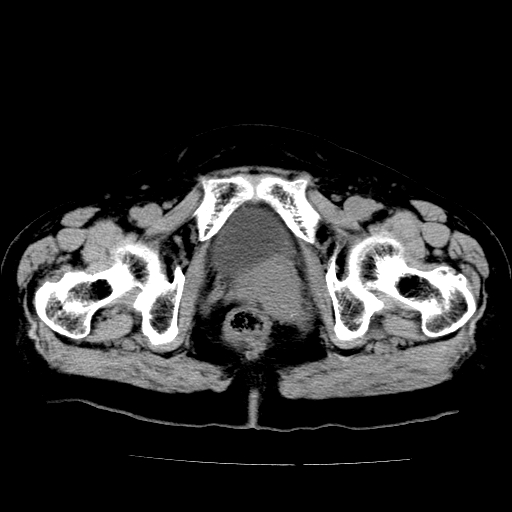

女,73岁,阴道流血一周。

宫颈不规则增大;结合临床考虑宫颈癌。建议作mri检查

1\\老年妇女突发阴道流血,常见病考虑宫颈癌.本病例宫颈部显示形态不规则,密度欠均匀,支持考虑宫 颈癌,建议mri 或阴道超声坚持

2\\但是盆腔两侧尚未见到明显肿大淋巴结等转移征象

宫颈不规则增大,左后方可见结节状突起.支持宫颈癌.

宫颈壁明显增厚,左侧为甚,宫颈癌待排,建议宫颈涂片细胞学检查。

宫颈不规则增大,周围脂肪间隙毛糙,结合临床考虑宫颈癌,盆腔内未见肿大淋巴结。